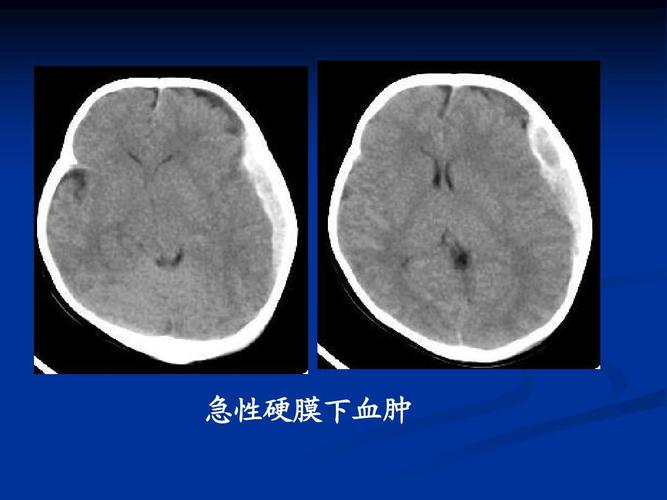

急性硬膜下血肿

急性硬膜下血肿ct图片

硬膜下血肿ct表现